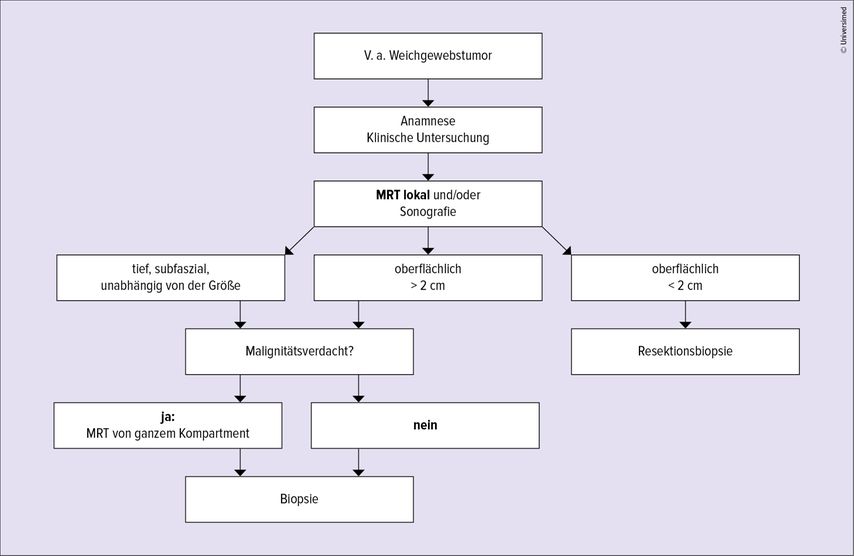

Am Anfang einer jeden Diagnostik steht die Anamnese, gefolgt von einer klinischen Untersuchung. Da 99% der benignen Weichteiltumoren in oberflächlichen Strukturen liegen,1 sind sie einer klinischen Untersuchung und Palpation (eher benigne: weich und gut verschieblich; eher maligne: derb, hart und schlecht verschieblich) zugänglich und weisen eine Größenausdehnung von meist weniger als 5cm auf.1,5 Weichteilsarkome liegen in etwa ¾ der Fälle subfaszial und habeneinen durchschnittlichen Durchmesser von >5cm bis ca. 10cm.1,5 Besteht initial noch Unklarheit, kann die Sonografie als ubiquitär verfügbare, kostengünstige und dynamische Untersuchung Aufschluss bringen, ob eine weiterführende Abklärung invasiv oder nichtinvasiv nötig ist. Klar sollte an dieser Stelle sein, dass die kontrastmittelunterstützte Magnetresonanztomografie den Goldstandard in der Abklärung von unbekannten Raumforderungen vor allem in Bezug auf Weichgewebe darstellt und einer geplanten Biopsie immer voranzustellen ist. Die Biopsie und ihr Weg sind stets mit einem Tumororthopäden/einer Tumororthopädin zu planen, da sie bei einer eventuellen Resektion den operativen Zugangsweg vorgibt. Eine interdisziplinäre Absprache muss bei radiologisch unterstützten Gewebegewinnungen (CT-gezielt/sonografisch unterstützt) erfolgen. Wir schlagen die diagnostische Abfolge in Anlehnung an Hardes et al. vor, wie in Abbildung 3 angeführt.1 Zudem empfehlen wir bei jeder operativen Entfernung einer Raumforderung unklarer Dignität dringend, Gewebe zur histologischen Aufarbeitung zu versenden sowie bei bestätigter Malignität eine Staging-Untersuchung durchzuführen.